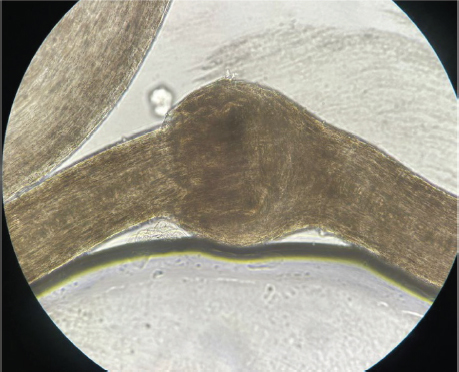

El cabello era frágil, seco y quebradizo. En una muestra de pelo de cuero cabelludo evaluada mediante microscopía óptica, se observaron fracturas transversales del tallo piloso, en las que la parte distal del pelo se invaginaba en la parte proximal, demostrando la presencia de tricorrexis invaginata, también denominada tallos o pelos en “caña de bambú” (Figura 5). El resto del examen físico resultó normal.

Figura 5. Tricorrexis invaginata vista desde el microscopio

Las manifestaciones clínicas pueden iniciar desde el nacimiento o luego de algunas semanas post parto. Al principio inicia con una eritrodermia ictiosiforme congénita y descamación la cual puede evolucionar a placas eritematosas descamativas conocido como ictiosis lineal circunfleja, esta permanece y decae a lo largo de la vida acompañada de prurito 10. Las manifestaciones de diátesis atópica pueden aumentar durante la niñez, incluyendo dermatitis atópica, rinitis alérgica, asma bronquial, angioedema y elevada producción de IgE 11. Las alteraciones en el cabello, tricorrexis invaginata o pelo en bambú, se debe a la invaginación de la porción distal en la porción proximal del pelo y es patognomónico, además se ven afectadas las cejas y pestañas. También se pueden presentar otros hallazgos al nivel del tallo piloso como tricorrexis nodosa, pili torti, moniletrix, cabello en palo de golf, pelo desflecado y cambios en el diámetro del pelo. Otros hallazgos son deshidratación hipernatrémica, desequilibrios electrolíticos, déficit neurológico, talla baja e infecciones a repetición 4, 7, 8. En el caso anterior el paciente presenta lesiones eccematosas características de SN y tricorrexis invaginata.